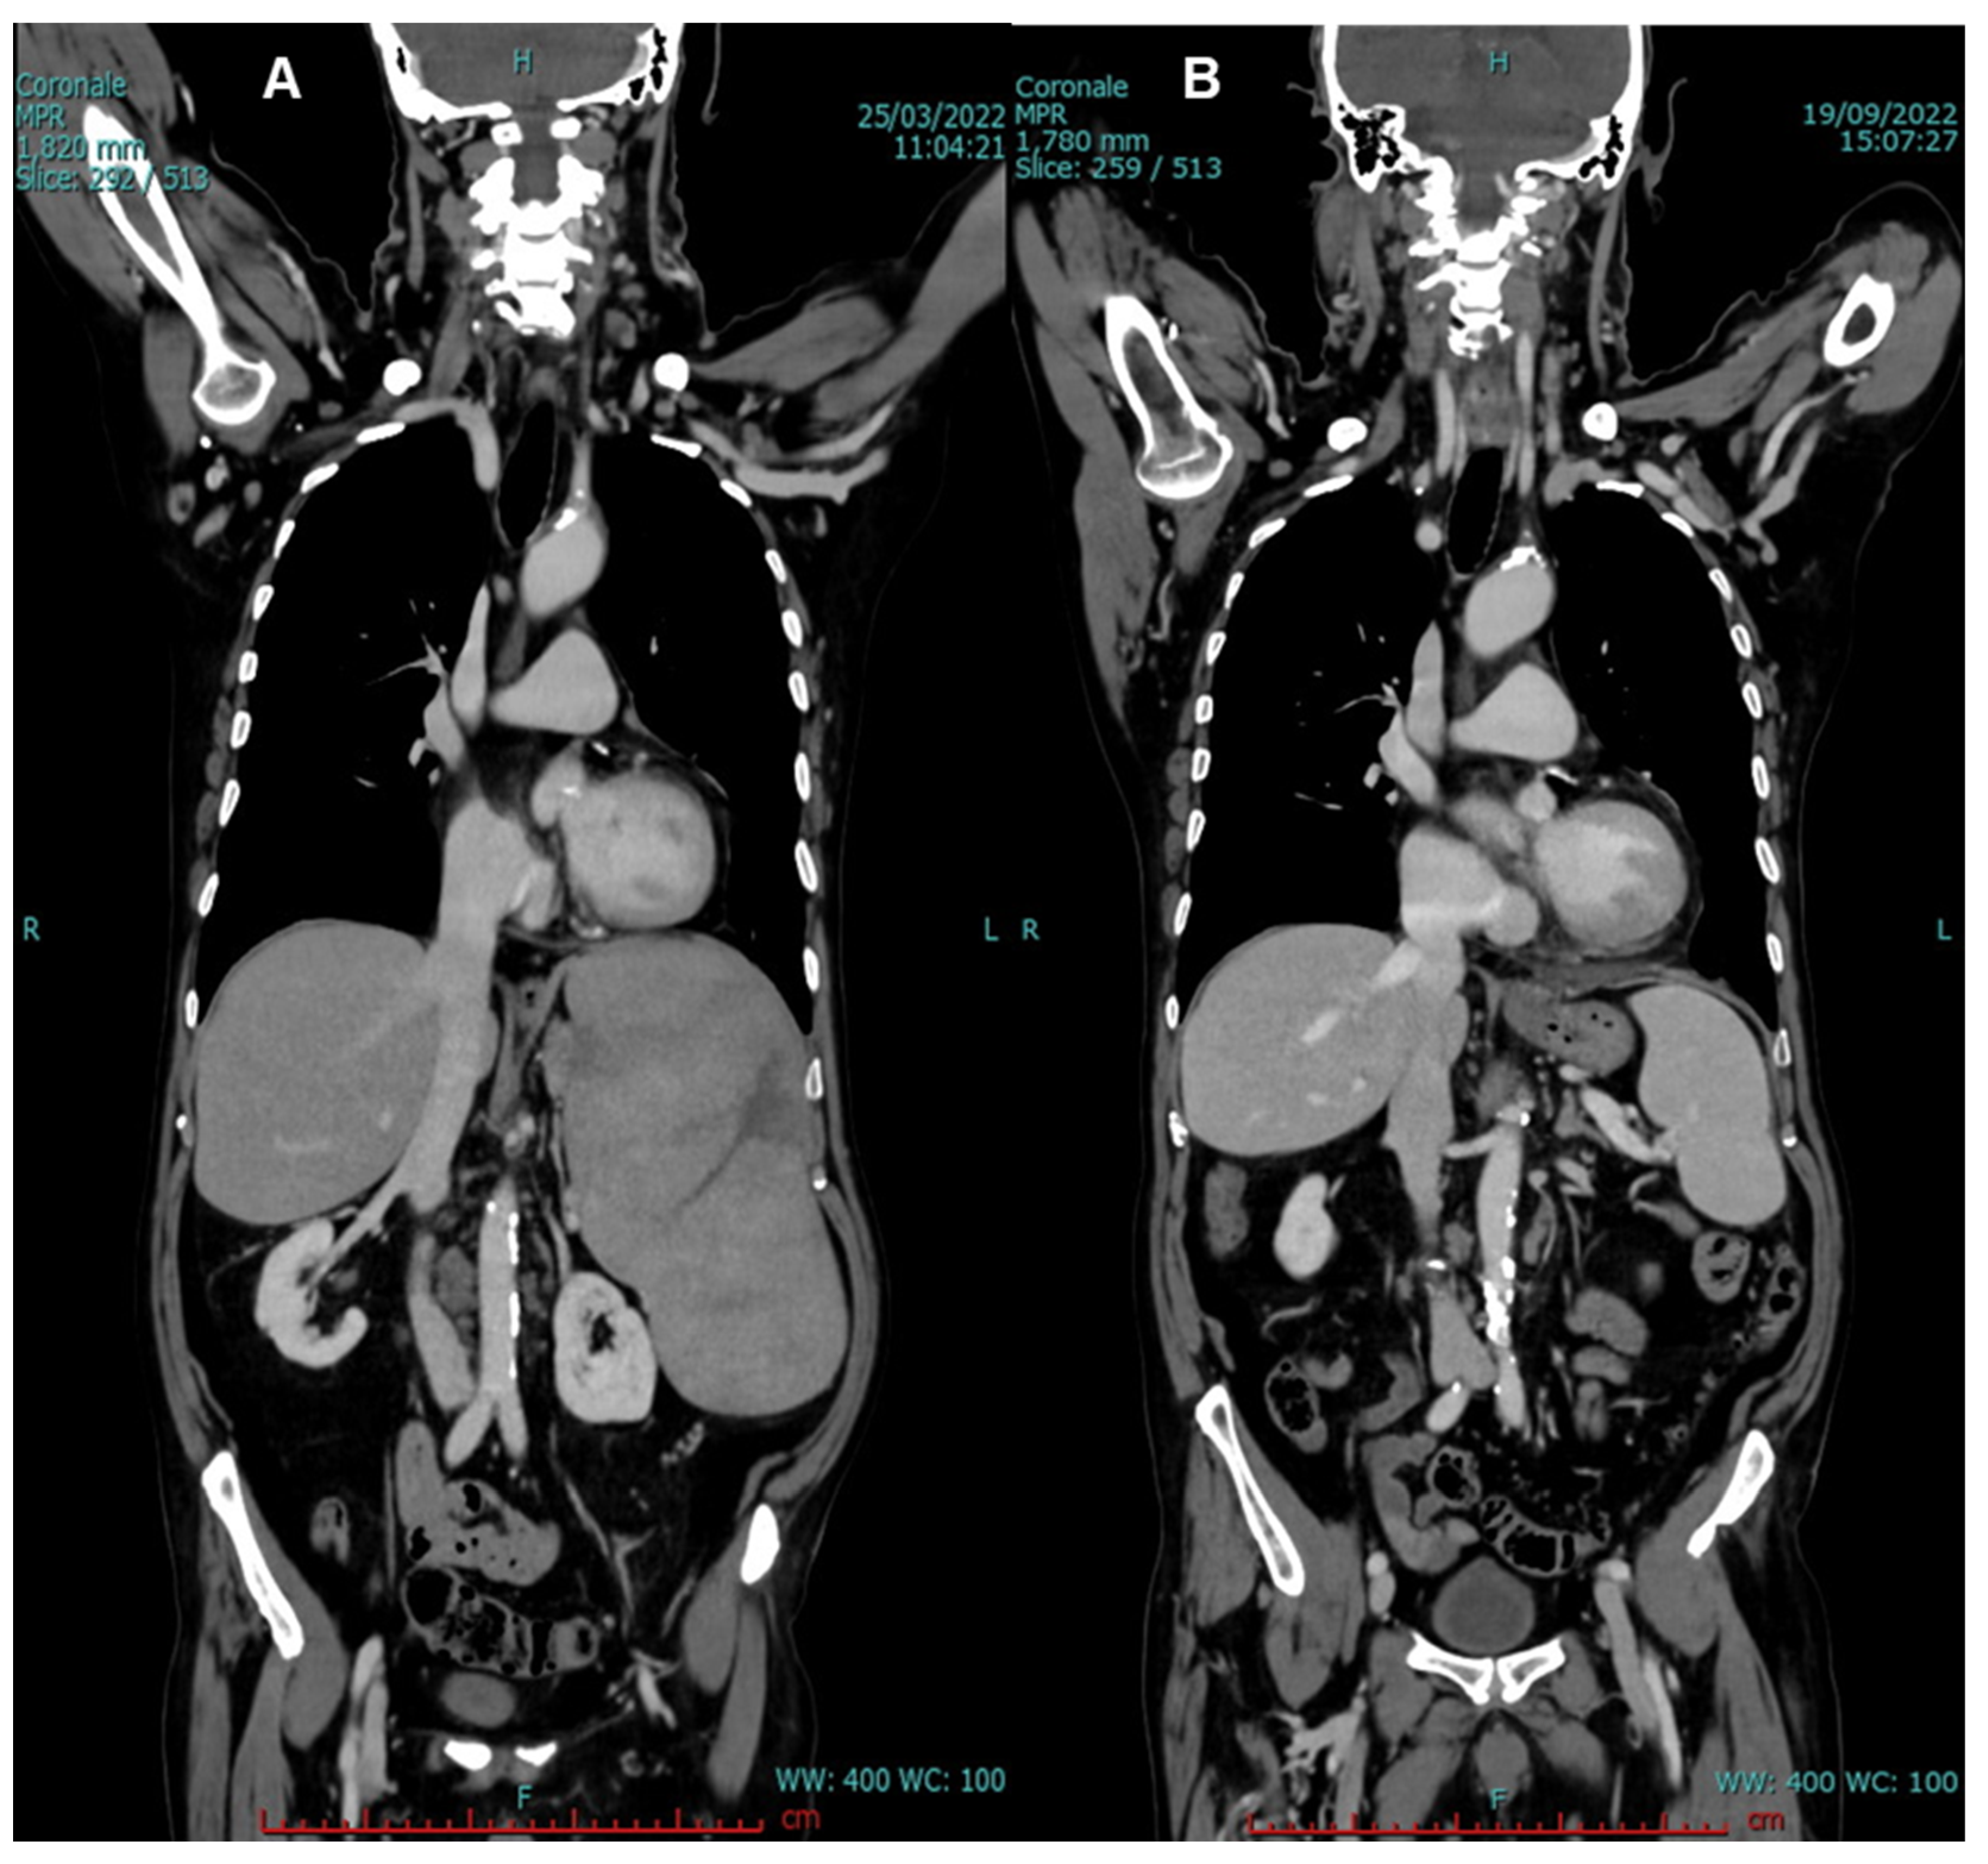

2. Case Presentation